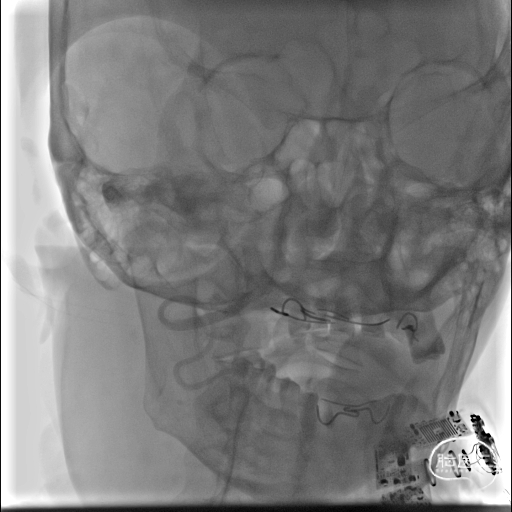

术前DSA影像:

右侧桡动脉穿刺置动脉鞘,泥鳅导丝配合6F 115cm Valent®颅内支撑导管内嵌行至右侧锁骨下动脉近右侧椎动脉起始段处,将导丝配合中间导管上行至椎动脉V3段,撤出泥鳅导丝,手推造影,显示:基底动脉中段可见重度狭窄,狭窄率约80%。